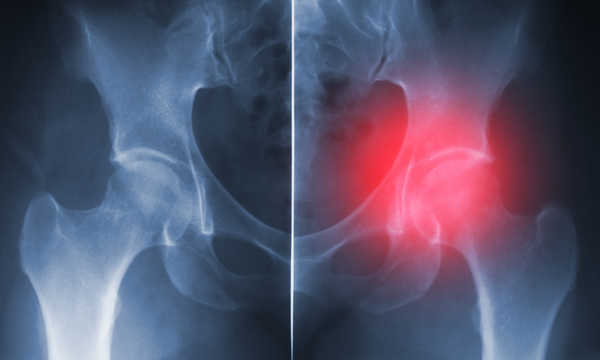

Naczelna Izba Lekarska podaje, że w Polsce rocznie wykonuje się około 48 tysięcy endoprotezoplastyk stawu biodrowego. Liczba ta jest dalece niewystarczająca, gdyż kolejka oczekujących jest dwa razy dłuższa. Z tego powodu protezy są wszczepiane zbyt późno, najczęściej wtedy, gdy doszło już do znacznego uszkodzenia powierzchni stawowych.

Ma to ogromny wpływ na jakość życia pacjenta, ograniczenie jego ruchomości i, co się z tym wiąże, spadek jakości tkanki kostnej. Nawet najlepsza proteza, wszczepiona u pacjenta z osteoporozą i ograniczonym zakresem ruchów, nie daje nadziei na jej długie przeżycie.